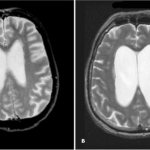

| Picture 1 |

Many therapists and cardiologists are well aware of this frequently occurring clinical phenomenon: in an elderly person without a rheumatic history, when listening to the heart, a rough systolic murmur is detected over the aortic points.

Often it is practically not interpreted in any way and is not reflected in the diagnosis. But sometimes, in an attempt to explain such an auscultatory picture, the doctor still makes something like this verdict: “atherosclerotic stenosis of the aortic mouth.” But we must not forget that a diagnosis is a formula for treatment, and further tactics largely depend on how correctly it is formulated. This applies to any diagnosis, and this one in particular. That is why it is necessary to seriously understand not only and not so much the validity of the term “atherosclerotic stenosis”, but what actually hides behind a “non-rheumatic” systolic murmur at the base of the heart. In the USSR, three main causes of acquired aortic stenosis were traditionally considered: 1) rheumatism, 2) infective endocarditis and 3) atherosclerosis. It was this triad, and, as a rule, in exactly this order, that migrated from manual to manual, from one textbook to another until the middle of this decade, while other prerequisites were given a place in the “and others” column. Most authors, after describing rheumatic and “septic” endocarditis in one form or another, mention atherosclerosis, which usually in old age can lead to the formation of calcified stenosis of the aortic valve [1].

In 1904, in the journal Archives of Pathological Anatomy, 28-year-old German physician Johann Georg Menckeberg described two cases of aortic stenosis with significant calcification of the valves [3]. He proposed to consider changes in the valves as degenerative, as a result of tissue wear followed by their “sclerosis” and calcification. Having apparently discovered something similar to what is shown in Fig. 1, he depicted in his article a deformed valve, in which, against the background of fatty degeneration, there are many calcareous deposits (Fig. 2). His correctness will be confirmed many years later, which will be reflected in the very term “degenerative calcified aortic stenosis.” But at the beginning of the century, I. G. Menkeberg’s article did not cause a significant resonance. And only after a decade and a half it will become the object of attention and form the basis of heated discussions that have been going on for a long time. The morphogenesis of the defect also caused a lot of controversy.